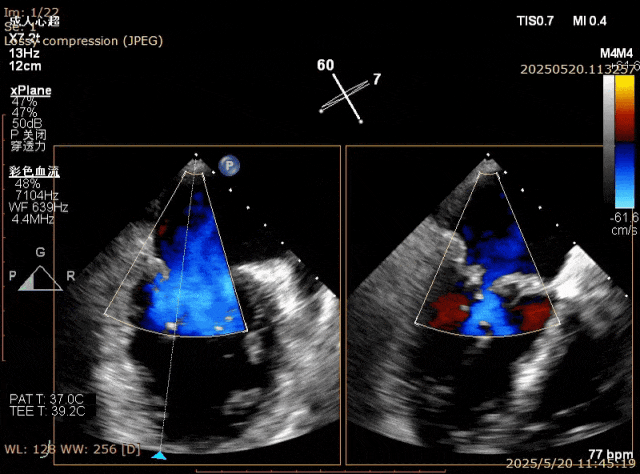

在经股静脉途径的TEER手术时,房间隔穿刺是一个很重要的基础步骤。有时候房间隔组织较韧较厚(多见于房间隔短穿刺位置需要靠后,或者外科房间隔修补术后),穿刺针通过之后要通过导引大鞘(GC)存在着较大困难,若强行推送大鞘可引起房间隔撕裂到左心房顶引起灾难性心包填塞。传统做法时使用外周球囊对房间隔进行扩张,但是不是每个导管室都常规配备外周球囊,且使用过大球囊仍可引起房间隔撕裂风险。我们提供了一种更简洁的方式,即使用导引鞘内芯和房间隔穿刺鞘两个管子(双管齐下)同时扩张房间隔穿刺口,再推送导引大鞘通过房间隔,无需额外器械,操作简单高效且安全(图1-4)。

图3. 沿着两根加硬导丝送入导引鞘内芯和房间隔穿刺鞘对房间隔进行扩张

图4. 顺利送入导引鞘通过房间隔